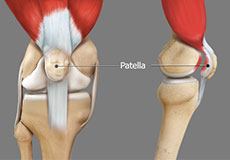

Patellar Instability

Any damage to the supporting ligaments may cause the patella to slip out of the groove either partially (subluxation) or completely (dislocation). This misalignment can damage the underlying soft structures such as muscles and ligaments that hold the kneecap in place.